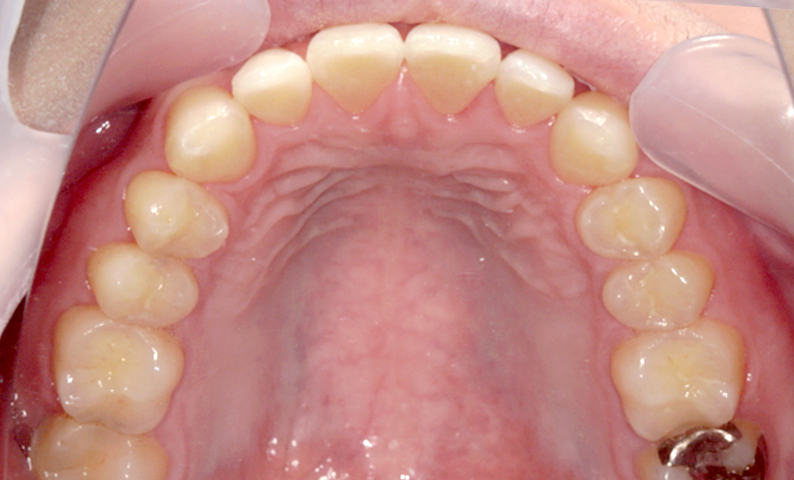

| 治療前 | 治療後 |

|---|---|

|